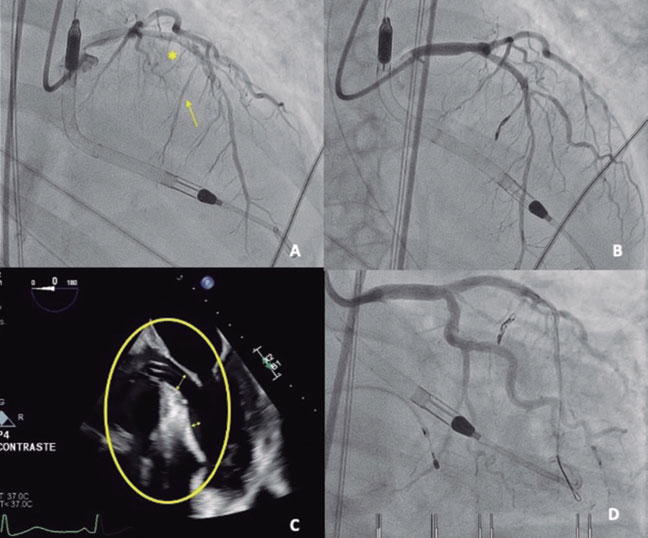

Implantation of the Impella-CP device (figure 1D, asterisk), with flow adjusted to 2.4 L/min (P4) to prevent suction, resulted in immediate hemodynamic and respiratory improvement, as well as a reduction in mitral regurgitation (figure 1E,F; arrows indicate the systolic S wave). A second septal branch (SB) showed extrinsic compression and was selected after confirmation of septal perfusion (figure 2A; arrow indicates second SB; asterisk: first SB). Two coils were deployed (figure 2B) due to potential reversibility, resulting in immediate flow reduction and DLVOTO improvement.

After 24 hours, the patient’s hemodynamic status deteriorated. Due to a slight increase in cardiac enzymes and recurrence of DLVOTO, alcohol ablation of the second SB was performed. Because basal septal contractility persisted (figure 2C, oval), occlusion of the first SB was also undertaken. Due to the impossibility of selective catheterization (figure 2D), a drug-eluting stent was implanted in the proximal left anterior descending coronary artery; thereafter, basal septal akinesia and mild mitral regurgitation were observed (video S2).